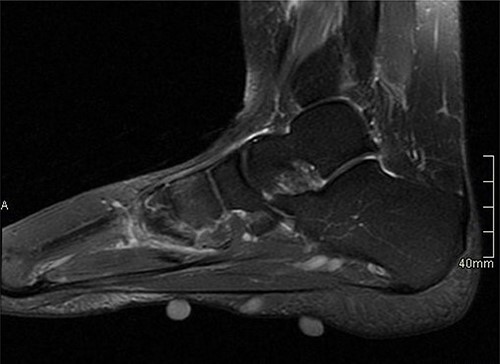

USS described this swelling in the plantar aspect of the midfoot as a well-defined, hypoechoic tender lesion within the plantar subcutaneous tissue measuring ~17 × 7 × 11 mm. More importantly, the lesion extended deep to the plantar fascia not arising from it, hence ruling out plantar fibromatosis (Fig. 1). In order to rule out any aggressive pathology, a magnetic resonance imaging (MRI) with contrast was arranged, which revealed a 2 cm by 5 mm tubular oblique lesion in the plantar subcutaneous fat. MR imaging was also able to rule out sinus tarsi syndrome and any internal derangements (Figs 2 and 3). She was referred to Orthotics for a medial support arch to help with pain. Since the exact characteristics of this lesion were still unknown, the case was referred to the Yorkshire Sarcoma Multi-disciplinary team (MDT). The outcome of this meeting concluded that there were no radiological features of a sarcoma. She still experienced an excruciating, sharp stabbing pain in her right foot. Pain score was 10/10. She opted for the surgical excision biopsy of the lesion. The post-operative period was uneventful with good healing of the wound. She was followed up 2 months, and with the histology findings, results revealed a rare soft tissue neural neoplasm in keeping of a neurofibrolipoma. The patient was happy with the overall outcome and was discharged. She was reviewed again after 2 years for a further foot and ankle problem in the other foot, and at the time of review, she was completely pain-free in the right foot with an excellent outcome.